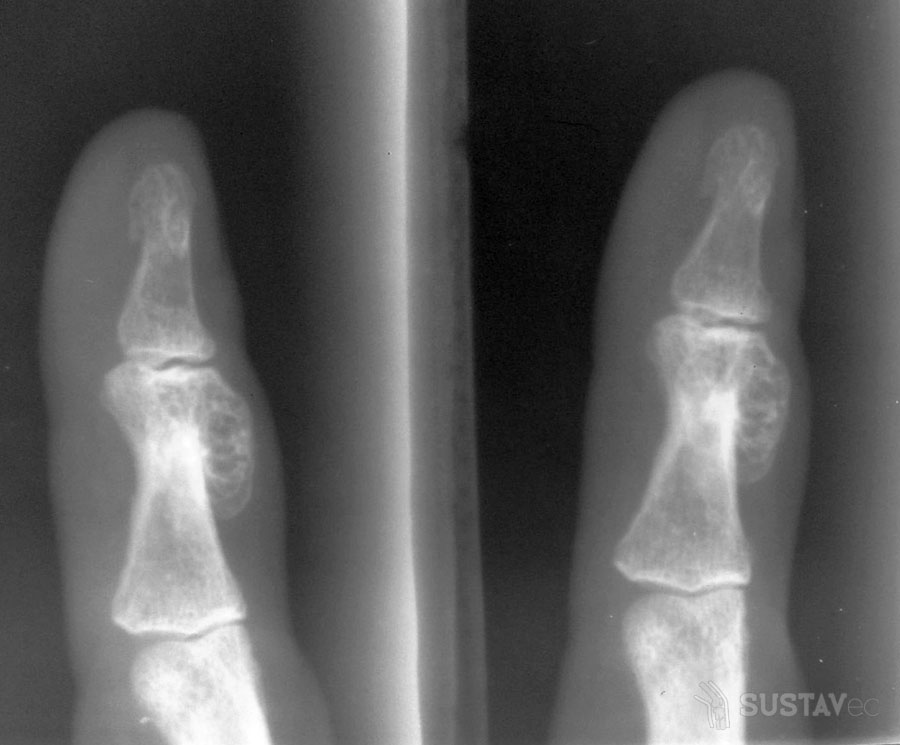

- Рентгенологическое исследование суставов. Полученные данные позволяют выявить деструктивные изменения костных тканей.

- межфаланговые суставчики – могут поражаться в первую очередь сразу несколько на одном или нескольких пальцах; развивается дактилит – воспаление пальца, и он приобретает вид сосиски; характерно также поражение конечных отделов пальцев и ногтей.